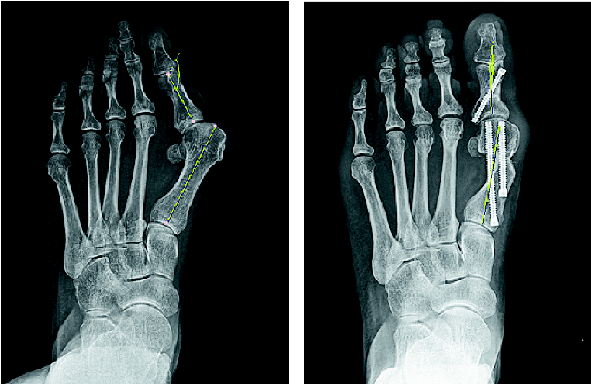

엄지발가락이 휘는 무지외반증은 불편한 신발에서 비롯되는 경우가 많다. 최근 최소침습수술이 도입돼 환자들의 만족도가 높다. 부산고려병원 남지호 과장이 환자와 상담하고 있다. 아래 작은 사진은 무지외반증 수술 전(왼쪽)과 후 엑스레이 사진. 부산고려병원 제공 엄지발가락이 휘는 무지외반증은 불편한 신발에서 비롯되는 경우가 많다. 최근 최소침습수술이 도입돼 환자들의 만족도가 높다. 부산고려병원 남지호 과장이 환자와 상담하고 있다. 아래 작은 사진은 무지외반증 수술 전(왼쪽)과 후 엑스레이 사진. 부산고려병원 제공

최근에는 회복이 빠르고 흉터도 적은 최소침습수술 MICA로 무지외반증을 교정한다. 5mm 이하의 작은 구멍을 3~4개 뚫어서 하는 수술이다. 남지호 과장은 “수술 시간도 짧아졌고 통증이 적어 수술 다음 날부터 걸을 수 있다. 회복이 빠르고 입원 기간도 짧다는 점에서 환자들의 만족도가 높다”고 말했다.

무지외반증 수술의 목적은 통증 완화가 우선이지만, 발이 남에게 보여지는 부분이라는 점에서 미용적인 면도 무시할 수 없다. 최소침습 교정수술 MICA는 길게 절개하지 않고 작은 구멍을 뚫어서 수술하기 때문에 미용적인 만족도가 높다. 이전에는 심하지 않은 변형에만 MICA를 적용하는 경우가 많았다. 하지만 최근에는 기술이 발전해 특수한 경우를 제외하고는 심한 변형에도 최소침습수술을 활용하는 경우가 많다.